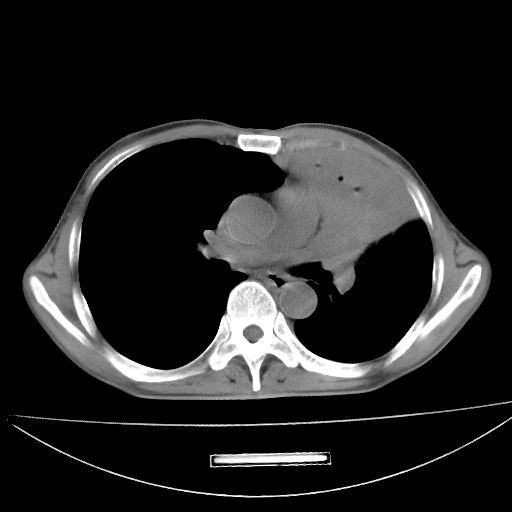

以下是引用杀毒软件在2009-4-28 17:58:00的发言:[br]考虑----左肺慢性肺脓肿形成继发上叶含气不良---抗炎后复查---待排肿瘤所致[br][br][本贴已被 杀毒软件 于 2009-4-28 18:01:26 修改过]